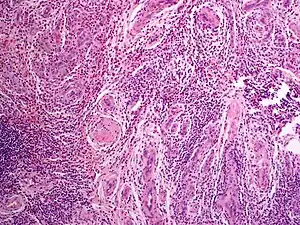

Angiolymphoid hyperplasia with eosinophilia

Angiolymphoid hyperplasia with eosinophilia (also known as:[1] "Epithelioid hemangioma," "Histiocytoid hemangioma," "Inflammatory angiomatous nodule," "Intravenous atypical vascular proliferation," "Papular angioplasia," "Inflammatory arteriovenous hemangioma," and "Pseudopyogenic granuloma") usually presents with pink to red-brown, dome-shaped, dermal papules or nodules of the head or neck, especially about the ears and on the scalp.[2]